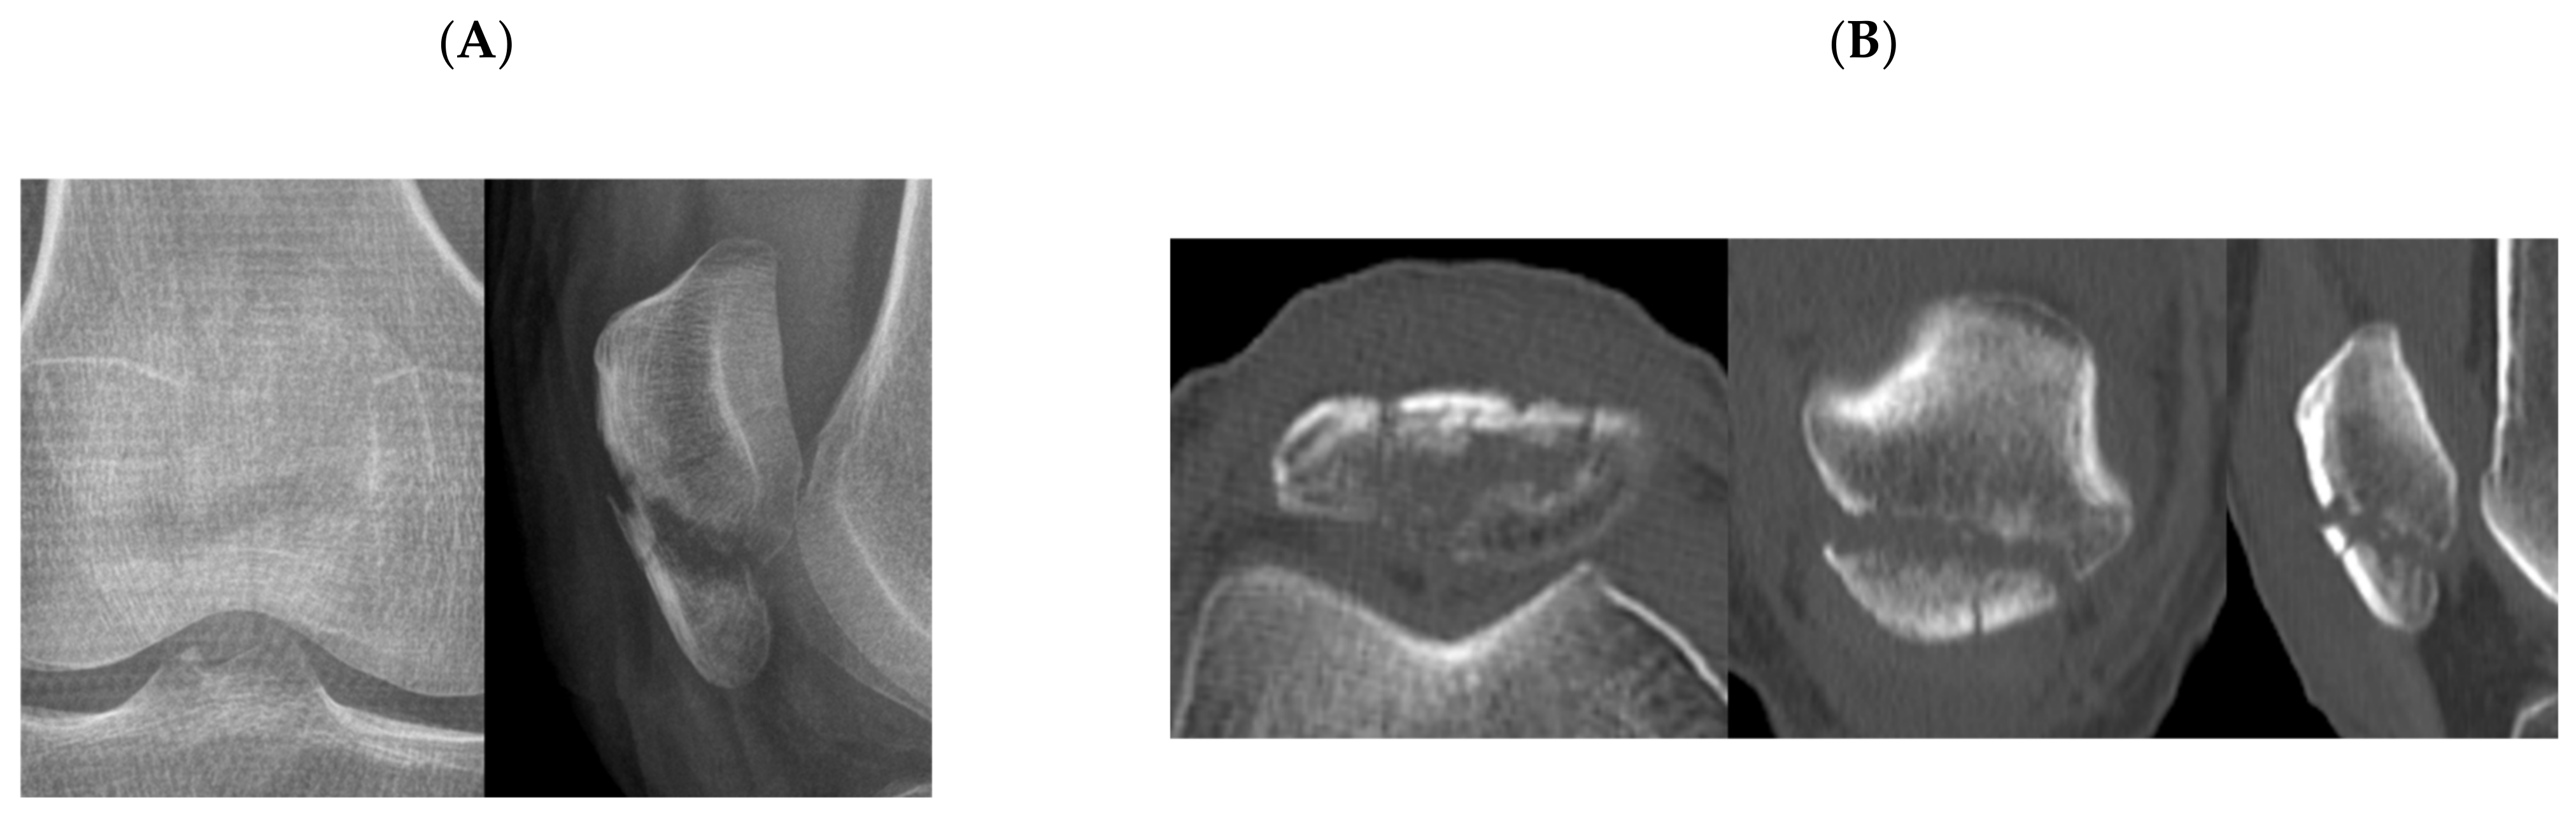

Figure 4. Plain radiographs (A), two-dimensional computed tomography (B), and three-dimensional computed tomography (C) of a patellar fracture with fracture lines of both horizontal and vertical fracture lines. The respondents chose either type A or B.